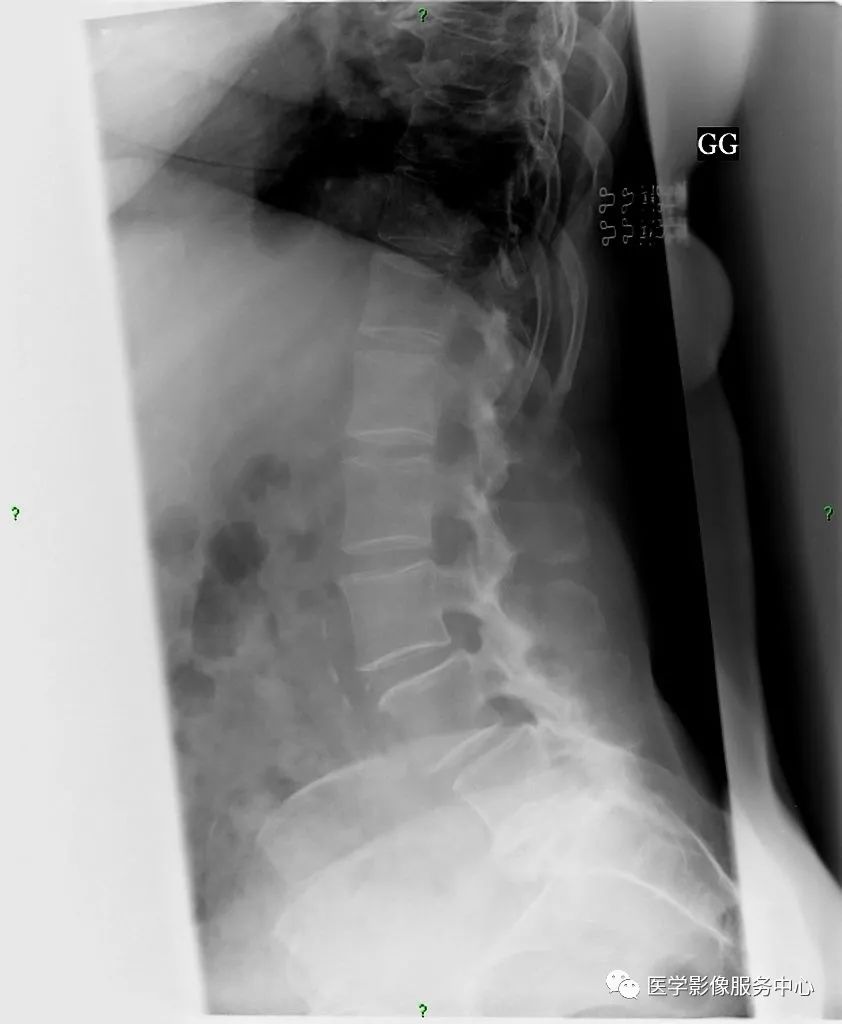

巴斯特鲁普 (氏) 病患者腰椎邻近的棘突相互靠近、撞击致相对缘骨质增生、硬化,棘突呈杵状增粗(反应性肥大),并列的棘突间表面变平及反应性硬化,甚至形成假关节。单节段棘突受累者少见,更多为多节段棘突受累。

X线、CT表现为棘突相对缘骨质增生,密度增高、肥厚,甚至形成假关节及棘突间积气。